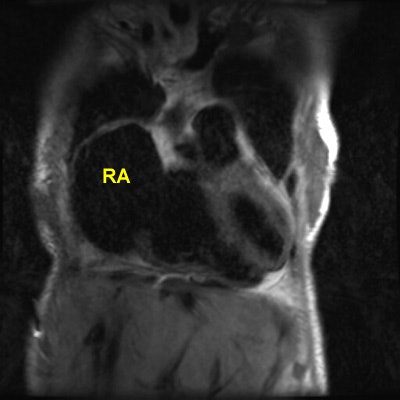

Rheumatic Fever

The patient shown below had a long history of valvular heart disease secondary to rheumatic fever. Both mitral and tricuspid valves were involved. There is massive right atrial (RA) dilatation. The left atrium is also massively dilated. Increased signal within the left atrium is related to slow flow.